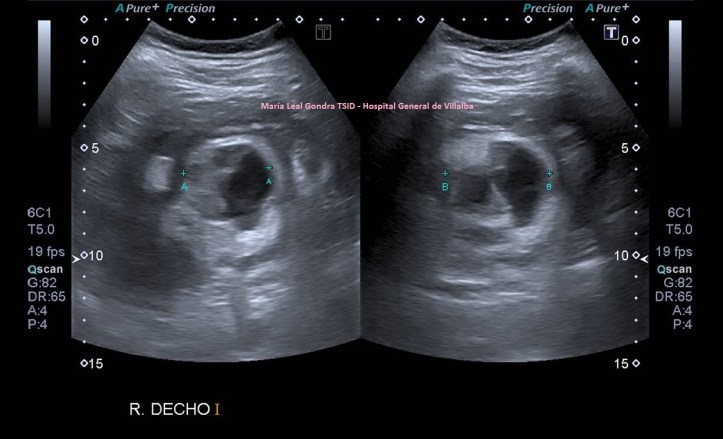

En la imagen 2 ves una lesión grande, redonda, de aspecto quístico, anecoica de bordes bien definidos y finos, con buena transmisión de sonido.

2

En la imagen 3,4 y 5 ves una lesión en la misma localización, ecogénica, sólida, heterogénea, redonda y de gran tamaño, lobulada. Tiene vascularización y es heterogénea. Flecha amarilla.

Ambas lesiones ubicadas en el polo superior del riñón derecho. más profundo que el polo inferior, normal, desde el punto de vista ecográfico, según la disposición de la sonda y la situación espacial del riñón en la anatomía humana de modo general, siempre a expensas de rotaciones y variantes de la normalidad.

Nos quedamos con la imagen 3 y 4, y en este caso observamos que es una lesión que la paciente ya tenía años atrás y que fue objetivada ecográficamente, de menor tamaño y que en tres años ha crecido considerablemente y que no ha sido tratada durante este tiempo por motivos que desconozco.

Un aperitivo de estos hallazgos en las imagen 7, sonde observas dos lesiones unidas, exofíticas, una quística y otra no, muy difícil de visualizar por las características del paciente y que debió ser diagnosticado por CT. Las flechas amarillas marcan una lesión quística, las rojas una lesión no quística, lo ves mejor en la imagen 8 donde puedes ver ambas medidas mejor definidas y medidas.